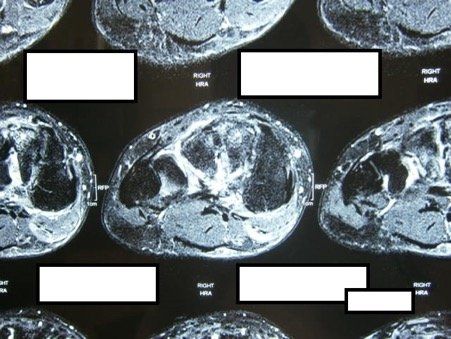

Midfoot arthritis refers to arthritis in the middle part of the foot. There are a number of joints that make up this part of the foot and arthritis in this area presents with degenerative changes. Degenerative changes are depicted by pain in the area, instability of the joint, narrowing of the joint space, osteophytes or bone spurs, cystic areas within the bone, damage to the joint cartilage, and laying down of extra bone.

Surgery for midfoot arthritis ranges from simple to more complex procedures. Surgery may involve a “clean-up” of the joint by removing damaged cartilage and bone spurs, resection of a part of the joint, fusion (stiffening) of one or more joints. Medical imaging, such as x-rays and MRIs are usually obtained prior to surgery to determine the extent of the injury and to plan for the proposed surgery.